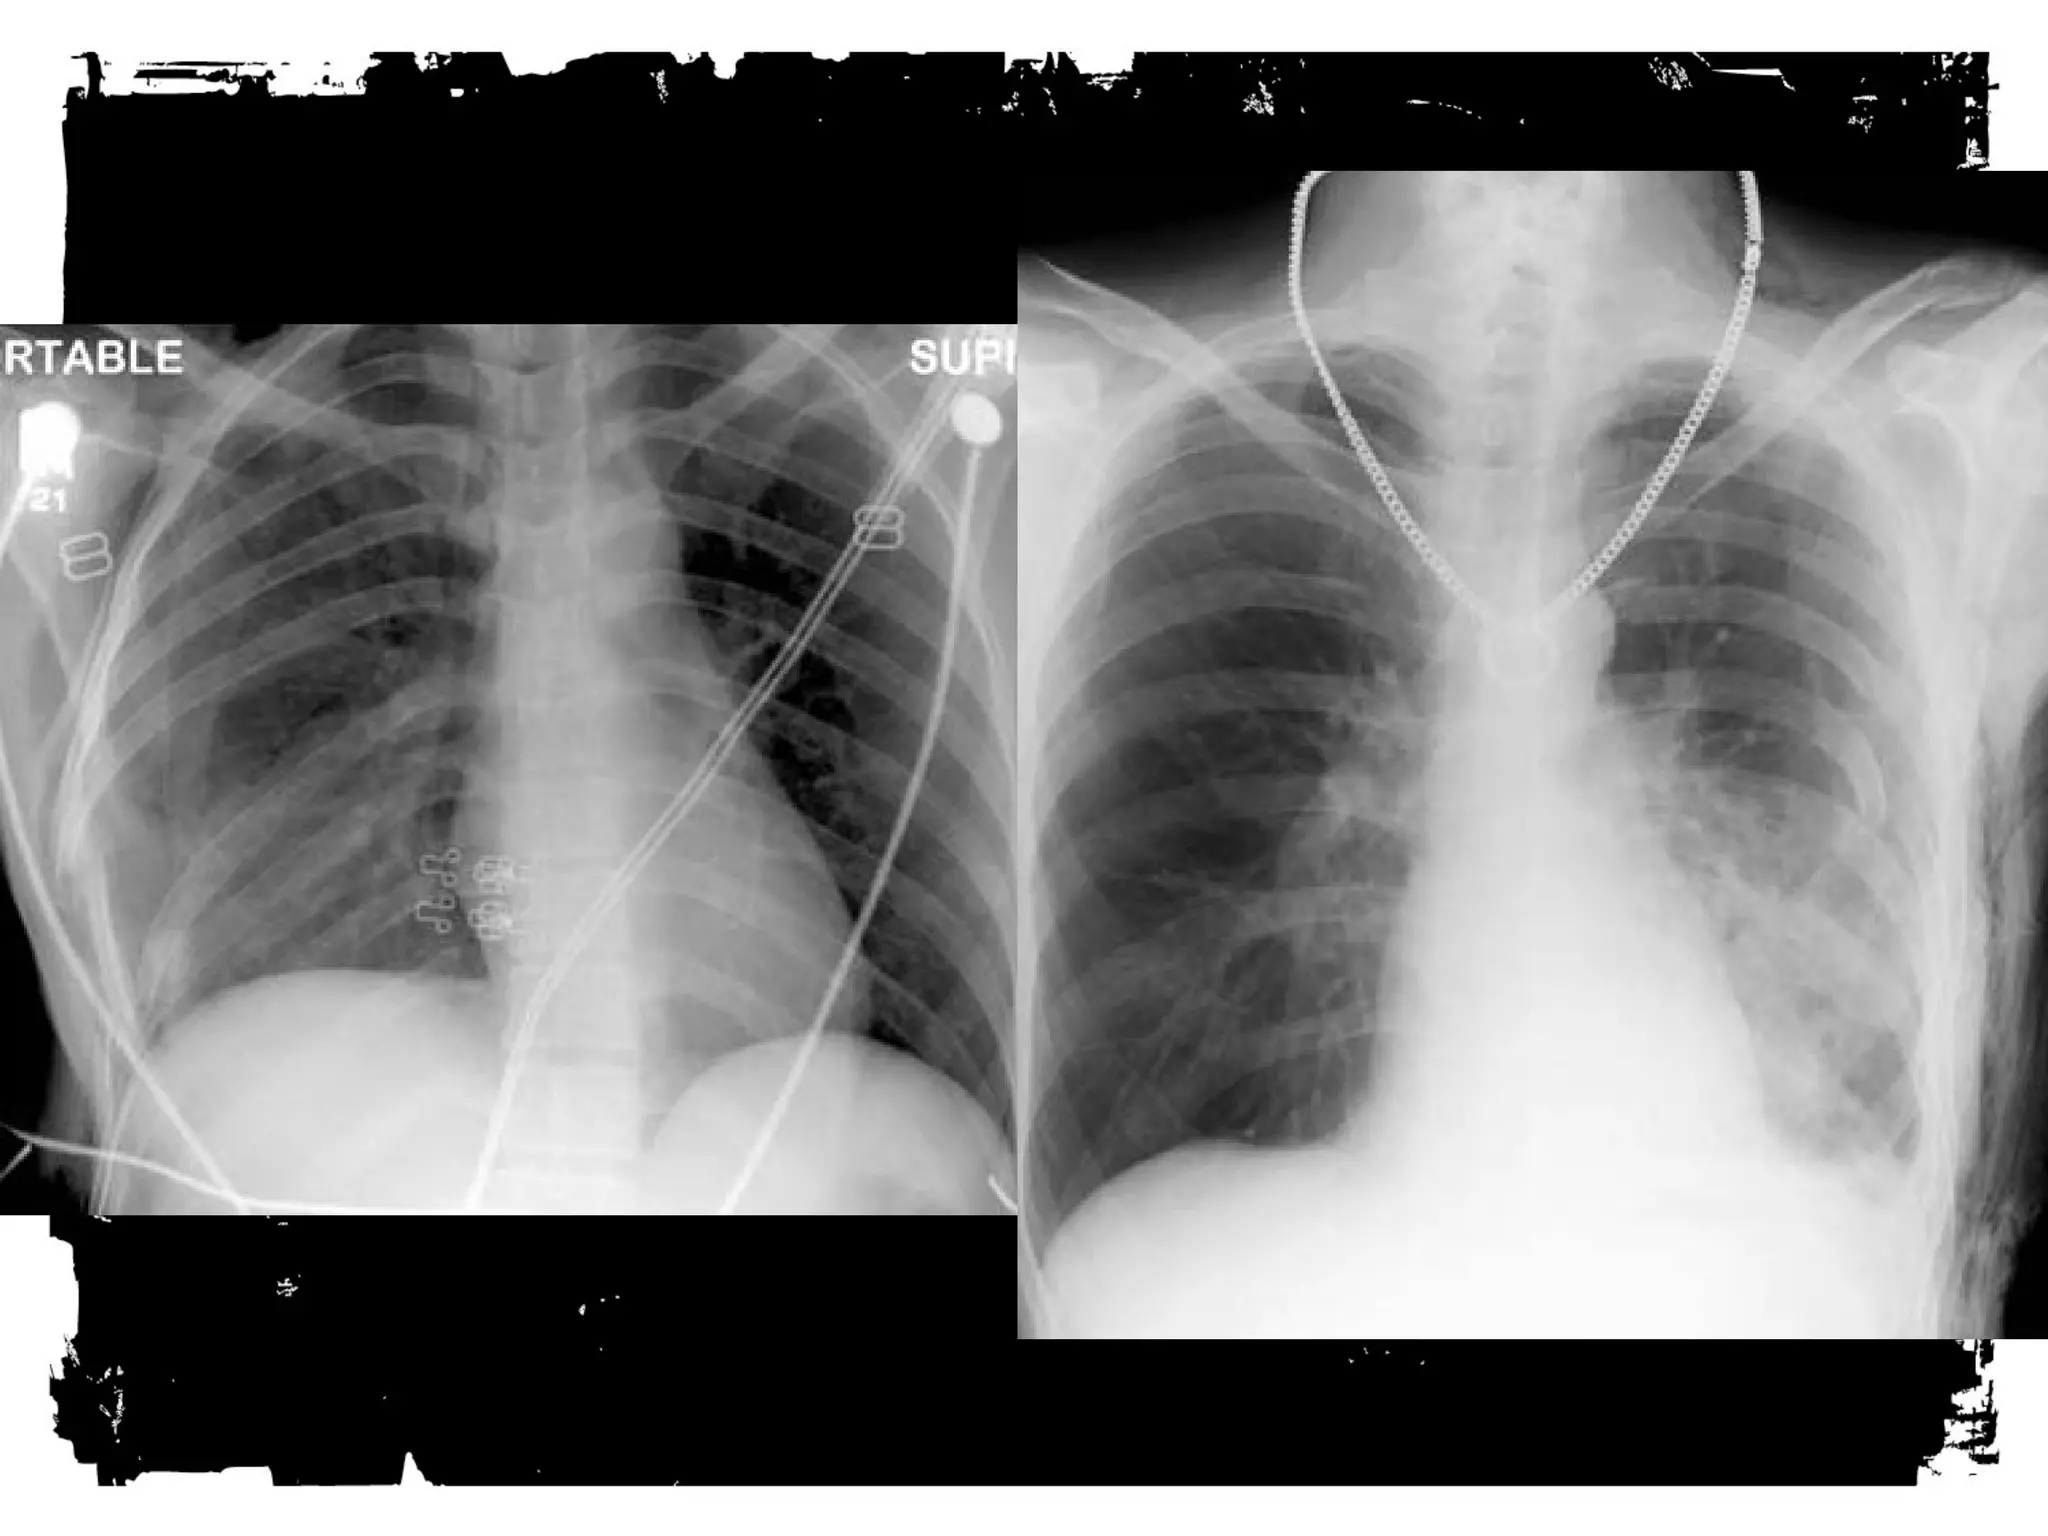

After chest trauma, imaging plays a key role for both,

the primary diagnostic work-up, and the secondary

assessment of potential treatment. Despite its well-known

limitations, the AP chest radiograph remains

the starting point of the imaging work-up. Adjunctive

imaging with CT, that recently is increasingly often

performed on MDCT units, adds essential

information not readily available on the CXR. This

allows better definition of trauma-associated thoracic

injuries not only in acute traumatic aortic injury, but

also in pulmonary, tracheobronchial, cardiac,

diaphragmal, and thoracic skeletal injuries.

Trauma Chest Radiograph

• Usually AP, often supine,

frequently in poor inspiration.

• So, a challenge to interpret.